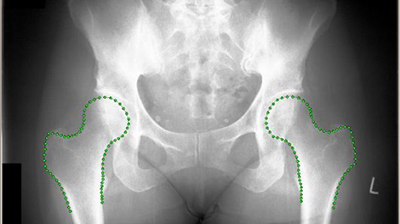

Несмотря на богатство технологических решений, которыми сейчас могут похвастаться буквально каждая из отраслей человеческой деятельности сегодня, не всё пока что идеально. К примеру, рентгеновские лучи не всегда показывают кости чётко отделяя...